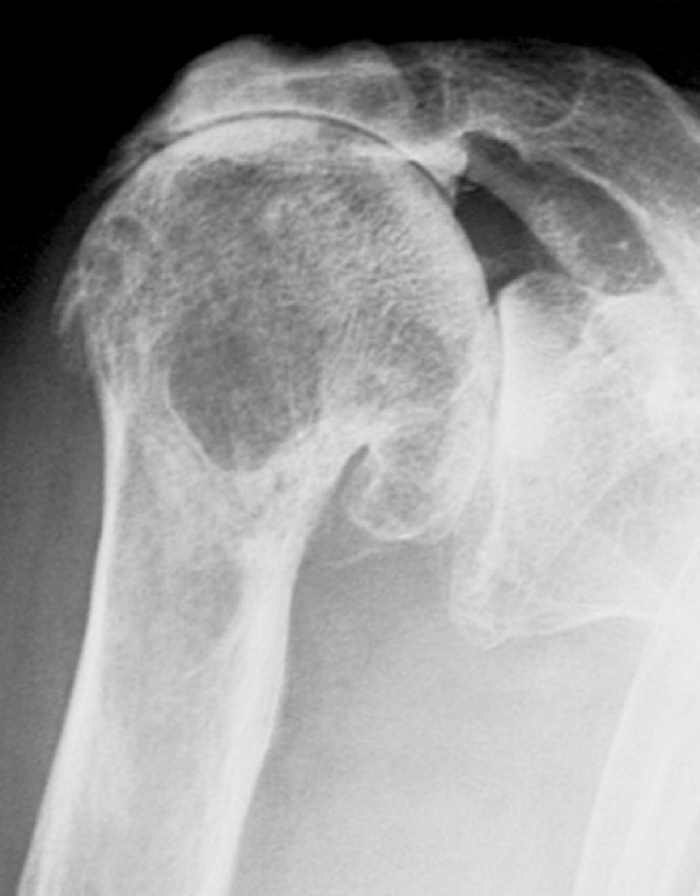

Некроз и деформация головки плеча.

Инструментально: на рентгенограмме - деформация головки.

МРТ выявляет на начальных стадиях.